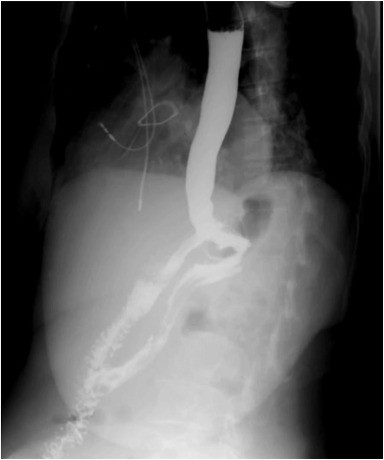

Upper GI series.

Following partial response to lactulose and rifaximin, and given the patient’s high surgical risk, she underwent EUS-guided gastrogastrostomy with placement of a 20-mm lumen-apposing metal stent (LAMS) (Hot AXIOS; Boston Scientific, Mass, USA) to restore foregut continuity. The procedure led to rapid normalization of ammonia levels (283 to 103 μmol/L), resolution of encephalopathy, and progressive weight gain. The LAMS was removed at 8 months; at 2-month follow-up, the gastrogastric fistula remained patent with sustained clinical benefit and normal ammonia levels (42 μmol/L).